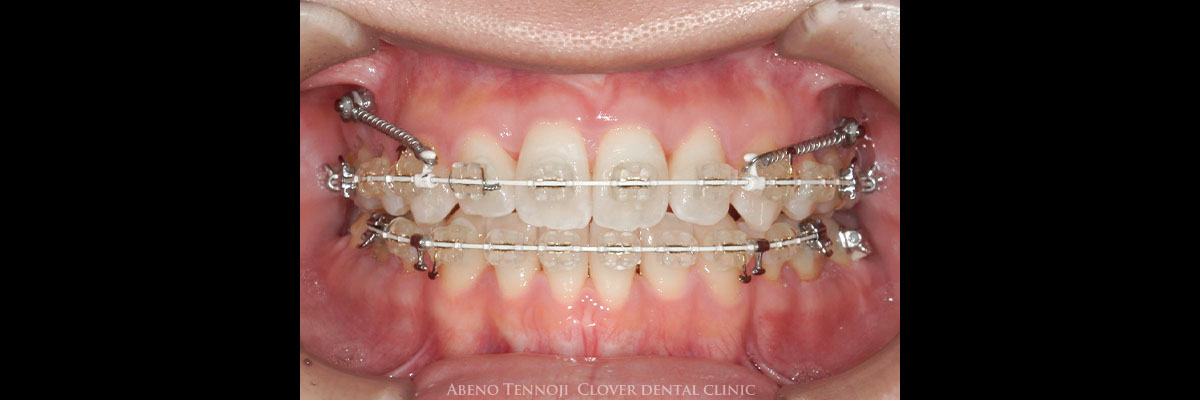

歯の表側にワイヤーを装着して歯並びを治す一般的な矯正方法です。

歯の表面にブラケットを付けて、そこへワイヤーを通して少しずつ歯を動かしていきます。